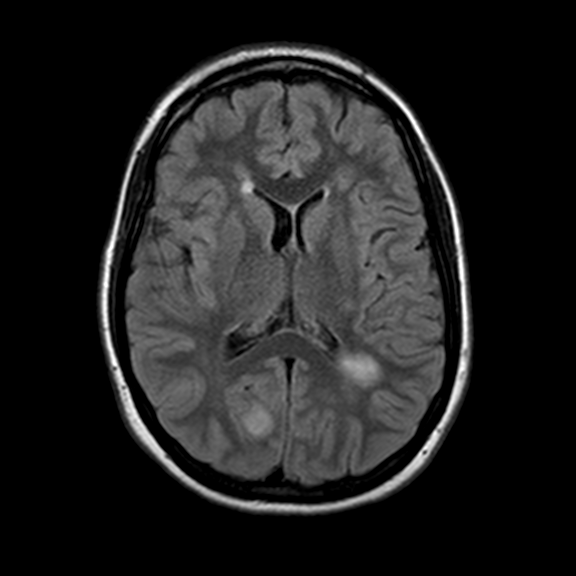

Bilateral asymmetric FLAIR hyperintensities

Peripehral open ring restriction on DWI not always seen as evidenced below